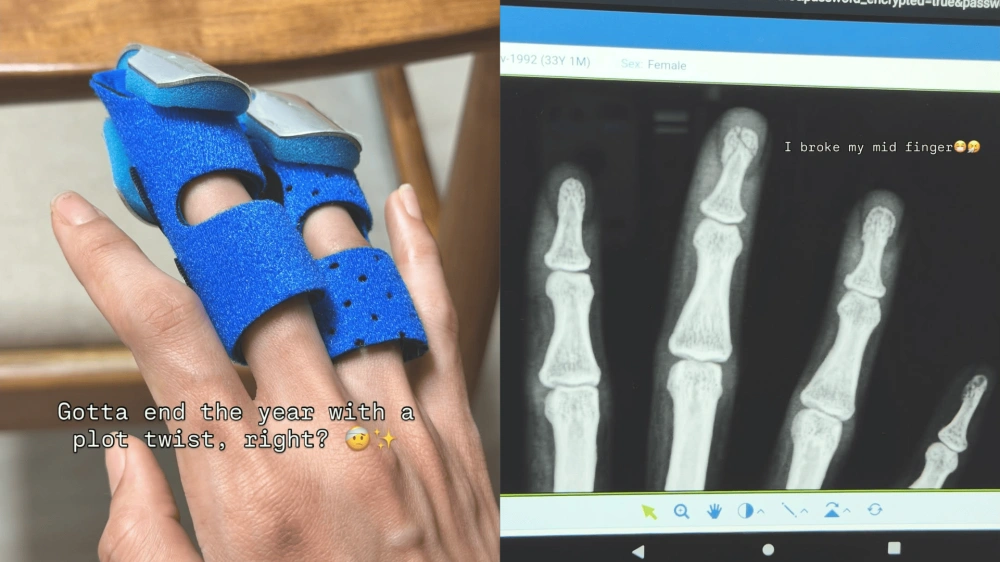

Melalui akun media sosial pribadinya, Sabrina membagikan kondisi terkini dirinya yang sedang terbaring mendapatkan perawatan medis. Ia mengungkapkan bahwa jari tengahnya mengalami keretakan tulang setelah terjepit pintu garasi besi di kediamannya pada Senin, 22 Desember 2025.

Insiden ini menjadi penutup tahun yang berat bagi Sabrina, yang tidak menyangka bahwa akhir tahun 2025 akan diwarnai dengan musibah fisik. Dalam unggahannya, ia turut menyertakan foto hasil rontgen yang memperlihatkan kondisi tulang jarinya yang retak.

"Hati-hati dengan apa yang kamu jadikan bahan bercandaan, sungguh. Kirim meme ke sahabat tentang melakukan satu hal bodoh terakhir sebelum 2026. Beberapa jam kemudian: jari tengah retak," tulis Sabrina dalam keterangan unggahannya.

Secara kronologis, Sabrina menjelaskan bahwa insiden itu terjadi sangat cepat saat ia hendak menutup pintu garasi yang terbuat dari besi berat. Tanpa sengaja, jari tengahnya berada di posisi yang salah sehingga terjepit dengan tekanan kuat.

Dampak dari jepitan tersebut ternyata cukup parah. Sabrina bahkan mengaku mendengar suara gemeretak tulang saat insiden itu berlangsung, yang menandakan adanya fraktur pada jarinya. "Iya, benar-benar meretakkan jari pas nutup pintu garasi besi, bahkan aku bisa dengar suara tulangnya retak," tambahnya.

Kejadian ini dianggap Sabrina sebagai sebuah "plot twist" yang tak terduga dalam perjalanan hidupnya sepanjang tahun 2025. Ia pun menuliskan pesan singkat yang menggambarkan kelelahan emosional dan fisiknya menghadapi tahun ini: "Dear 2025, udah ya, ampun."